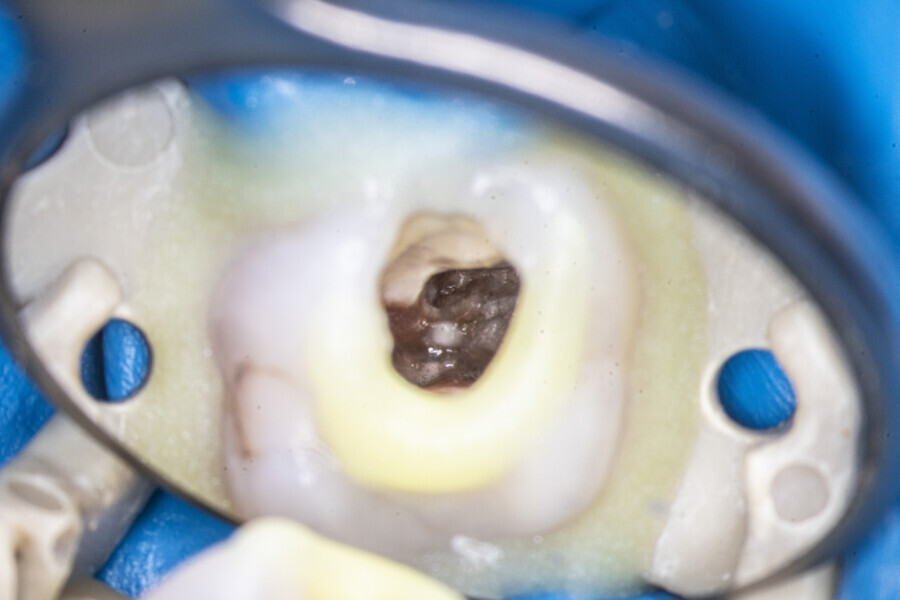

Case 2 (Figs. 27–36)

A 25-year-old female patient presented to the office owing to constant pain related to the mandibular left first molar. Pulp necrosis was diagnosed. After the emergency appointment, the patient was referred for complete treatment. The tooth was treated in the same manner as described in the previous paragraphs. After creation of the access cavity, the orifices were located. In the root chamber, the orifices of the MB, mesiolingual, DB, distomesial and distolingual canals were present. After pre-flaring and preparation of the middle third, the LPE enhanced irrigation protocol with the SkyPulse laser was performed. After the irrigation protocol in the mesial root, the irrigants started to flow between lingual and buccal canals. Such an observation suggested to the operator that some space in the isthmus had been created. It is worth mentioning that at this stage apical enlargement was not performed. Final preparation of all five canals was performed with the reciprocating file, and the final irrigation protocol was performed as in the previous case. The radiograph clearly revealed that the isthmus space was filled with the sealer. The radiograph and CBCT image revealed that there were four portals of exit in the mesial root.